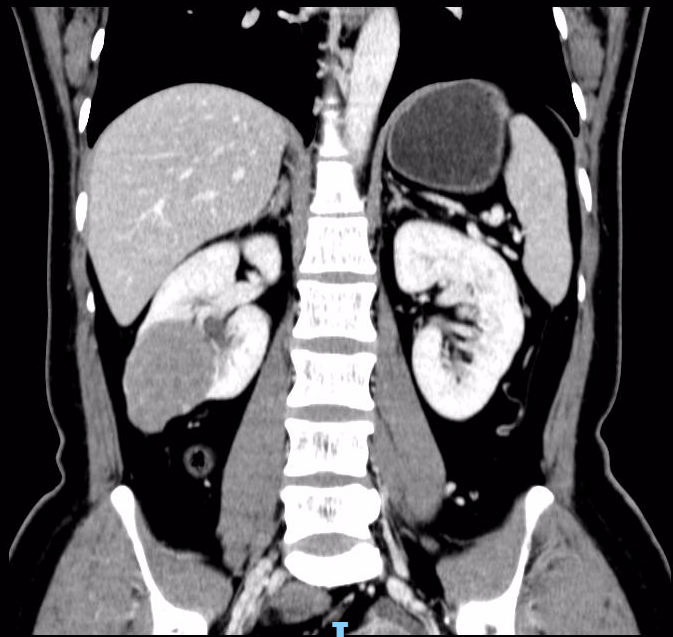

患者,女性,36岁。因10天前体检彩超发现右肾实质性占位病变,进一步行增强CT检查提示“1.右肾占位,轻度强化;性质待定,拟肿瘤性病变可能,肾癌(乳头状肾细胞癌)?建议结合临床相关性实验室检查。”。为进一步手术治疗入院。术前为患者行全息影像重建做好手术规划,考虑肿瘤局限,适合行肾癌部分切除术(单纯切除肿瘤而保存大部分健康的肾脏实质)。患者恢复良好,术后4天出院。术后病理提示右肾嫌色细胞癌。

CT所见